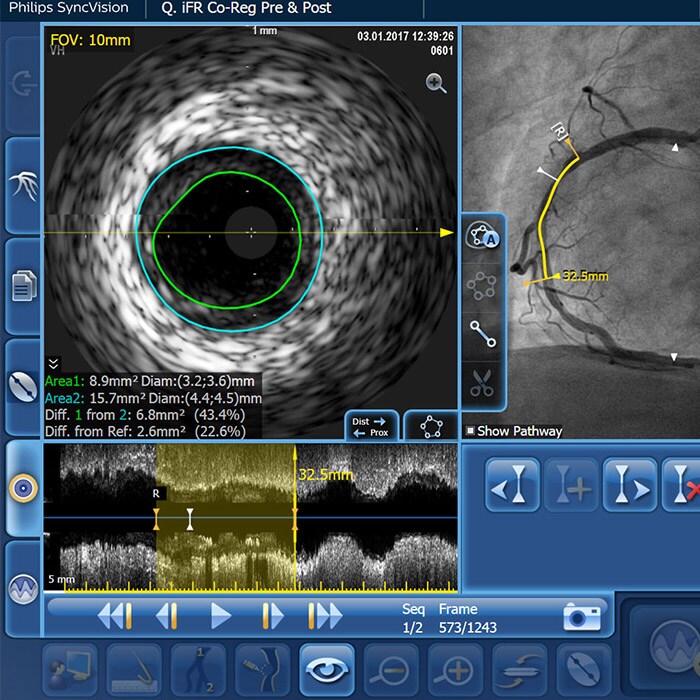

– Diffuse CAD may be underestimated by evaluation with coronary angiography.

– Determining reference vessel sizing can be challenging when the vessel is diffusely diseased.

IVUS-guided vs. angiography-guided outcomes3

Advanced tools for optimal PCI outcomes